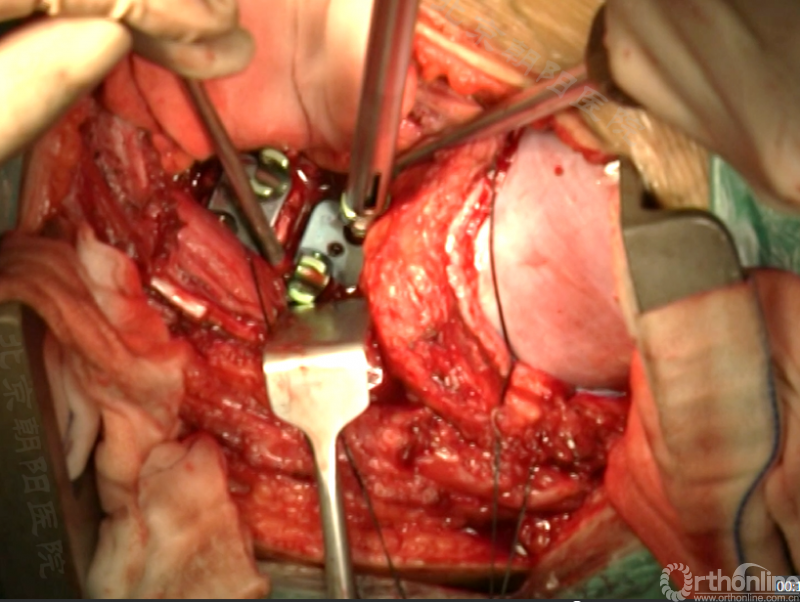

胸腔侧、腹腔侧螺钉全部置入后,骨移植物植人的越靠近后纵韧带或者纤维环的后缘越好。

将预先折弯的金属棒先置入背侧。

椎间融合器经前方置入凹侧,确保腰椎前凸的恢复和冠状面畸形的矫正,将剩下的骨移植物置入椎间隙内。

置入腹侧金属棒。

使用双棒系统时先安装背侧的棒,可进行90°的去旋转,也可以直接通过前方螺钉矫正冠状面和矢状面的畸形,然后固定后方的棒,可进一步通过加压矫正冠状面畸形。

矫正后神经检测未见异常术中唤醒患者下肢活动良好,术中透视矫正效果满意、内固定位置良好。根据手术具体情况放置合适尺寸的横连接加强内固定。